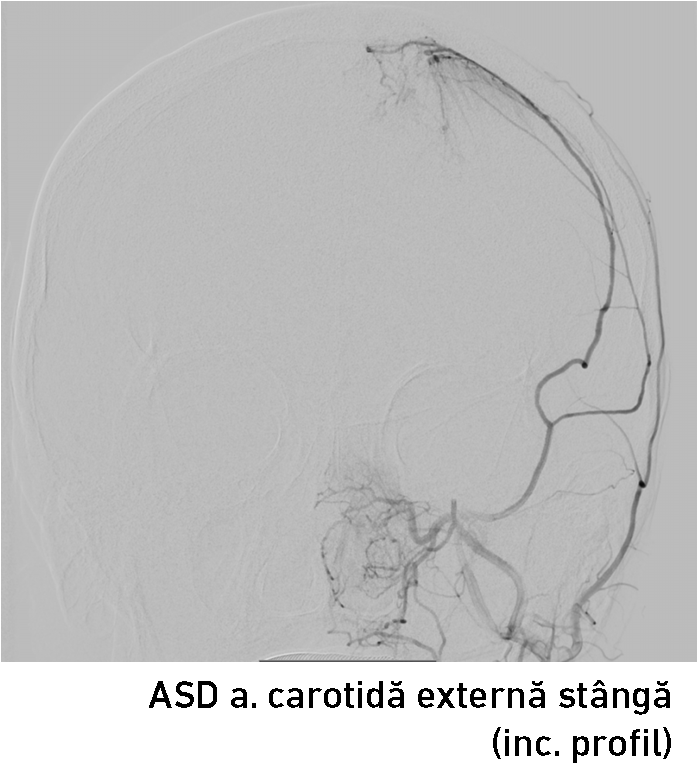

A fost decisă realizarea angiografiei cu substracție digitală a vaselor capului și gâtului preoperator, pentru aprecierea vascularizării tumorii și posibilităților tratamentului endovascular.

Angiografia clasică diagnostică a confirmat existența unui blush tumoral (fig. 3-4) – leziunea fiind alimentată de artera meningee medie (AMM) stângă și artera temporală superficială stânga (ramuri ale arterei carotide externe stângi). Echipa medicală a decis realizarea unei embolizări preoperatorii pentru a reduce hemoragia intraoperatorie și diminuarea riscului de recurență tumorală (care este dublu la meningioamele parasagitale !). Hemoragia intraoperatorie reprezintă un factor de risc major și poate împiedica chirurgul în realizarea unei exereze radicale a proceselor tumorale voluminoase.